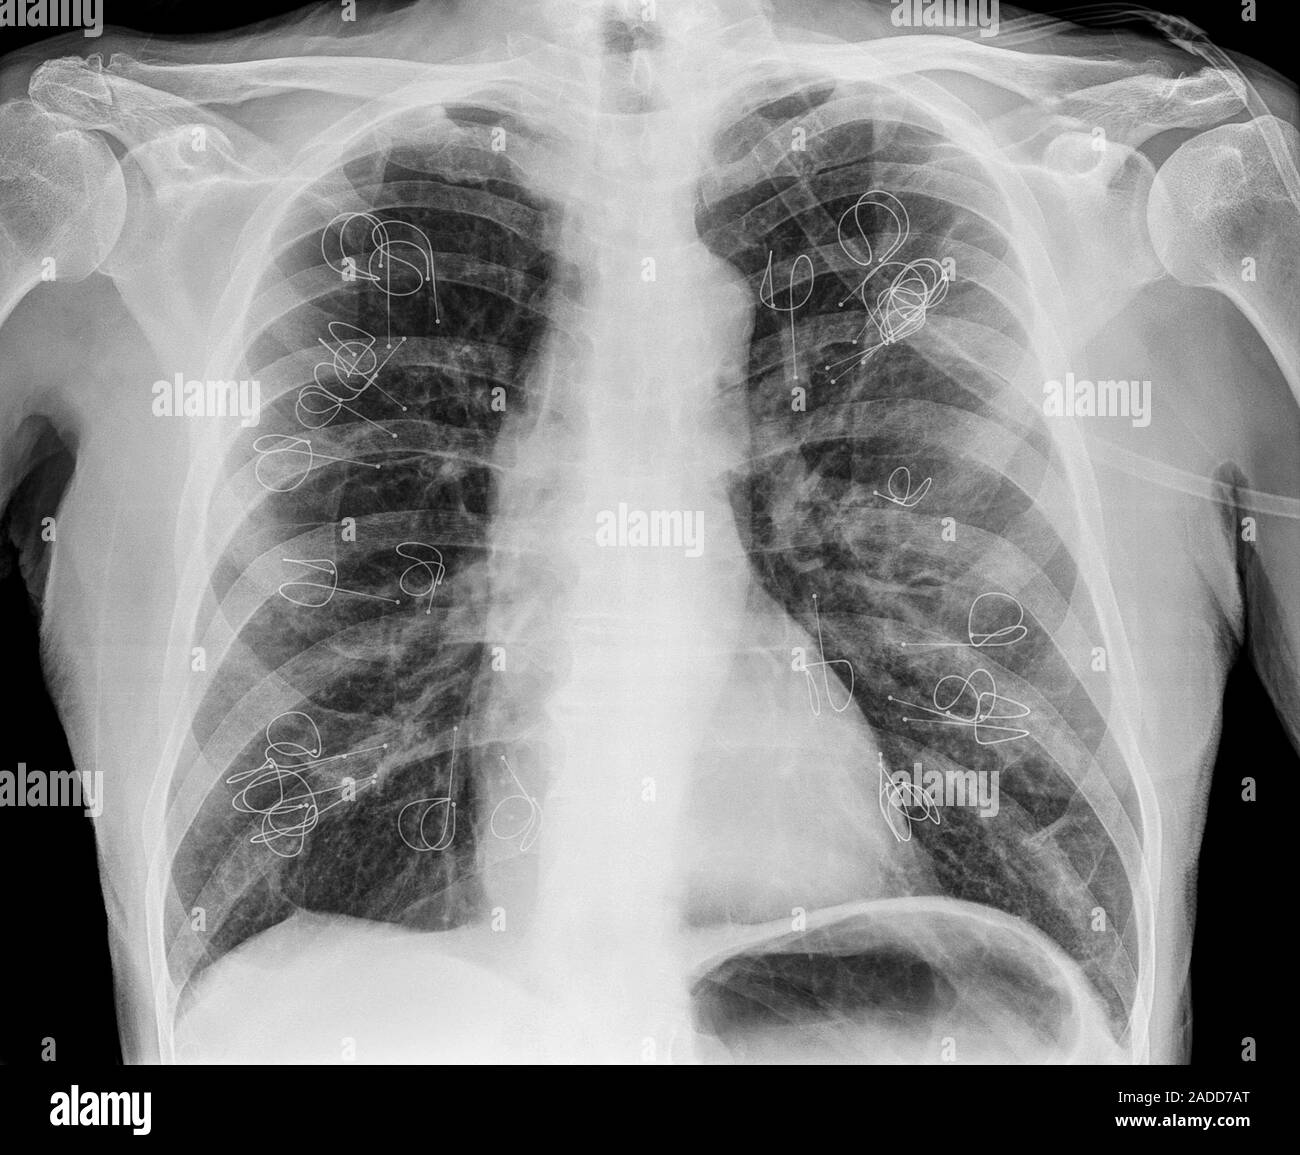

Implanted lung volume reduction coils. Xray of the lungs of a patient Coils In Lungs We report the medium term effectiveness. Lung volume reduction using nitinol coils is a bronchoscopic intervention inducing regional parenchymal volume reduction and. The lung volume reduction coil treatment is a minimally invasive bronchoscopic treatment option for emphysema patients who suffer from. The lung volume reduction coil treatment is a minimally invasive bronchoscopic treatment option for emphysema patients who. The pathophysiological. Coils In Lungs.

From www.alamy.com